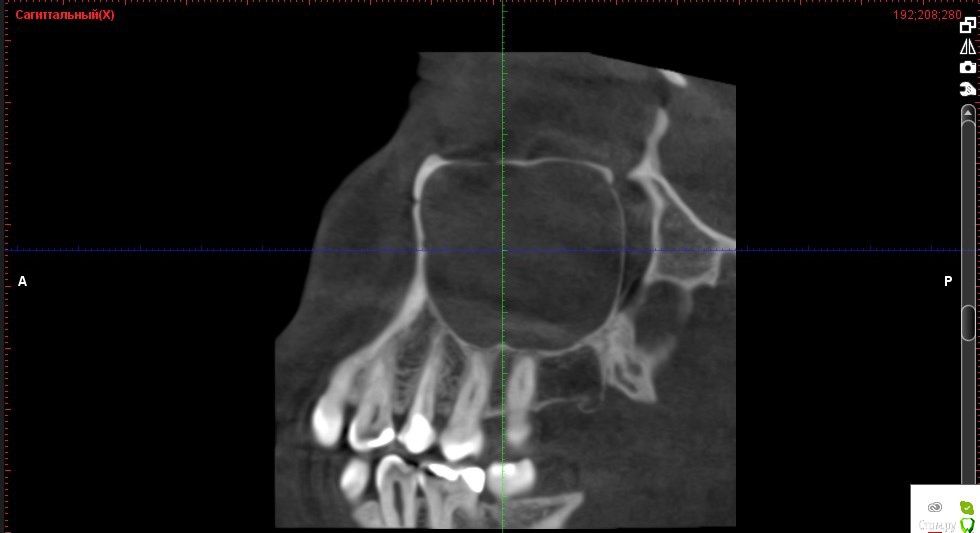

Verasss Опубликовано 8 октября, 2016 Автор Поделиться Опубликовано 8 октября, 2016 КТ от 08.09. Извините, что в таком виде, надо менять ОЗУ. Ссылка на комментарий

Verasss Опубликовано 28 октября, 2016 Автор Поделиться Опубликовано 28 октября, 2016 Добрый вечер! Ещё раз попытаюсь прикрепить скриншоты КТ от сентября. Если качество совсем не устраивает, подскажите, пожалуйста, какие сделать снимки?К сожалению, программа не позволяет вывести снимки на полный экран и заскриншотить в более хорошем качестве. Ссылка на комментарий

Verasss Опубликовано 28 октября, 2016 Автор Поделиться Опубликовано 28 октября, 2016 еще снимки Ссылка на комментарий

Verasss Опубликовано 28 октября, 2016 Автор Поделиться Опубликовано 28 октября, 2016 и еще Ссылка на комментарий